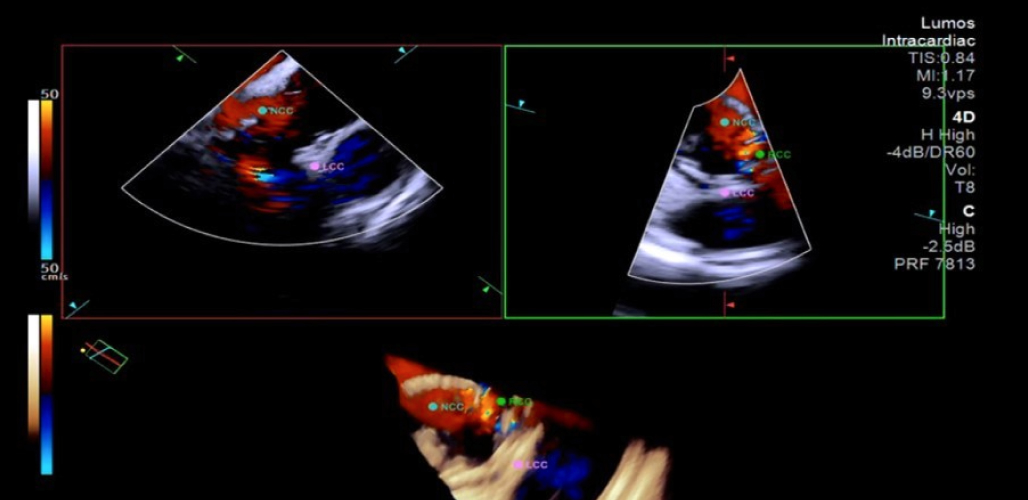

중앙대광명병원이 국내 최초로 4D(4차원) 심장내 초음파를 활용한 경피 적 대동맥판막 삽입술(Transcatheter Aortic Valve Implantation, TAVI)을 성공적으로 마쳤다. 순환기내과 임홍의 교수와 조준환 교수는 지난 6월 13일, 4D 심장내 초음파를 이용한 경피적 대동맥판막 삽입술 2케이스를 성공적으로 실시했다. 이번 시술은 중앙대광명병원 심장뇌혈관병원이 주최한 국제심장혈관 시술 영상포럼(K-imaging 2025) 중 라이브 케이스로 진행됐다. 전 세계 13개국의 순환기내과 중재시술 전문의들이 지켜보는 가운데, 경피적 대동맥판막 삽입술(TAVI)과 같은 고난도 중재시술에서 4D 심장내 초음파의 유용성과 안전성을 직접 시연해 국내외 전문의들로부터 큰 호평을 받았다. 4D 심장내 초음파는 심장 내부의 구조를 실시간으로 정밀하게 보여주는 고해상도 영상 기술로, 해부학적 정보를 다양한 각도에서 입체영상으로 제공한다.